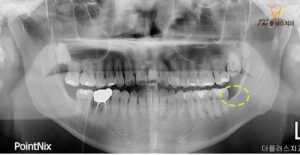

정밀한 진단을 위해

파노라마 사진을 촬영해 보았습니다.

사진을 보시게 되면 수평 매복 되어있는 모습을

보실 수 있는데 이 종류의 사랑니는

정상적인 치열에 대해 수평으로 위치하고 있어

다른 치아를 압박하고

치조골을 훼손할 수 있기 때문에

이러한 사랑니들은 보통 발치하는 것이 좋습니다.

조금 더 정밀한 진단과 안정적인 발치를 위해

CT를 촬영하여 사랑니의

정확한 맹출 방향과 치근의 휨 정도,

신경과 중첩된 모양 모두 정밀히 파악하여

발치를 진행하기로 하였습니다.